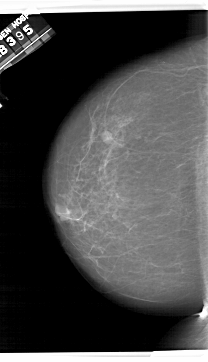

A_1409_1.LEFT_MLO

LEFT_MLO LINES 6541 PIXELS_PER_LINE 4186 BITS_PER_PIXEL 12 RESOLUTION 43.5 NON_OVERLAY